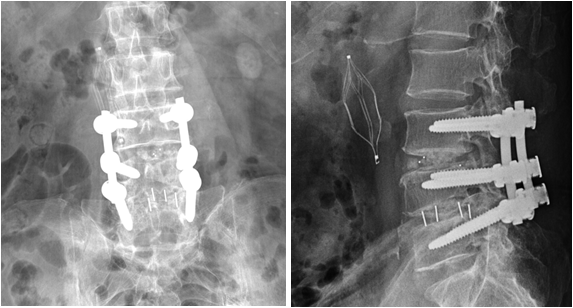

腰椎间盘突出症是一种常见的退行性腰椎病变,早期主要以保守治疗为主,包括改变不良姿势、加强腰背肌锻炼、止痛、营养神经、理疗等。若出现腰腿痛症加重,下肢肌力下降,二便功能障碍,保守治疗不能缓解,需考虑手术治疗。有很多人会问,手术治疗后是不是会一劳永逸,永不再发呢?答案是否定的。因为腰椎间盘突出症手术后还会面临两大问题: (1)腰椎间盘突出症术后复发,与年龄、肥胖、退变程度、骨质疏松症以及其它基础病等息息相关。 (2)腰椎间盘突出症术后邻椎病(也就是挨着原来突出节段椎间旁旁边的椎间盘再次突出而发病),近年越来越常见,主要原因是相邻腰椎不稳定或相邻椎间隙活动度异常增大等原因所导致,常需再次手术治疗。让我们看一个病人的治疗经过。 病人杨某某,男,70岁,因腰椎术后疼痛12年,加重2月入院治疗。病人2010年前因腰椎间突出症外院行腰45后路减压植骨融合内固定术,术后患者时有腰背部酸痛不适。2017年腰痛症状加重,伴下肢放射痛,再次行腰45翻修术+腰34后路减压植骨融合内固定,术后腰痛及下肢放射痛症状明显缓解。2022年6月腰痛加重,合并骨质疏松症,行密固达静滴治疗。同年8月腰痛再次加重,外院就诊提示内固定松动,再次行翻修及腰2到骶2节段内固定手术。术后腰骶部仍反复疼痛,下肢放射痛,行走不利。 杨先生入院后经温针灸、推拿手法行气活血,小针刀松解腰骶部瘢痕黏连,中药泡洗、热奄包外敷、中药内服等治疗加速淋巴回流,最终腰骶部疼痛基本消失,恢复了双侧下肢的行走功能,对治疗效果非常满意。 腰椎间盘突出症手术治疗不是一劳永逸,因此术后做好防护、避免相邻节段椎间盘再次突出引起临椎病显得非常重要。腰椎手术后需注意避免外伤、剧烈活动、久坐久蹲、弯腰劳累;要坚持锻炼腰背部肌肉;适当控制体重;出现腰腿部不适,要及时复查;调整心理,放松心情正常融入生活。 文中介绍的病人由于前三次手术创伤较大,手术部位存在严重疤痕组织,且内固定装置对腰骶部软组织刺激较大。瘢痕是人体修复创伤的产物,在正常的伤口愈合中,胶原的合成与降解维持平衡。病理性瘢痕组织发生过度增生,病人术后容易形成质地较为坚硬的增生性瘢痕,常感觉疼痛。术后增生性瘢痕形成后会影响淋巴回流,造成软组织肿胀。 这种多次手术后的情况,病人多不愿意再次接受手术治疗。此时应该针对软组织进行治疗。而小针刀治疗正是治疗软组织的有效方法。小针刀是在传统中医理论以及解剖学、生理病理学、现代生物力学等现代医学理论指导下, 融合了中医的针灸针和西医的手术刀的长处而形成的中医微创技术,以组织剥离的手法, 达到松解黏连的目的。针刀直径一般只有0.5~0.8mm, 损伤非常小;加之针刀的针柄和针刃是在同一个平面内, 可以通过针柄控制针刃在人体内的方向, 治疗非常安全,越来越受到病人的欢迎。而术后瘢痕黏连,是针刀临床的最佳适应证之一,进针点一般在瘢痕局部及周围。针刀的治疗原理主要是通过闭合性松解微创操作,切开瘢痕、分离粘连与挛缩、疏通堵塞,从而改变软组织的病理状态,恢复软组织和骨关节的力学平衡,以消除症状。 腰椎间盘突出症手术治疗并不是一劳永逸的。手术之后,在做好防护的同时,配合小针刀等其它有效治疗手段也显得非常重要。 附图: 2010年L4/5术后,2017年正侧位摄片 2017年6月L3/4、L4/5术后正侧位摄片 2022年8月腰痛L2-S2术后,可见骶椎软组织覆盖薄弱 作者:上海中医药大学附属光华医院 康复科 王世辉 程少丹 延伸阅读